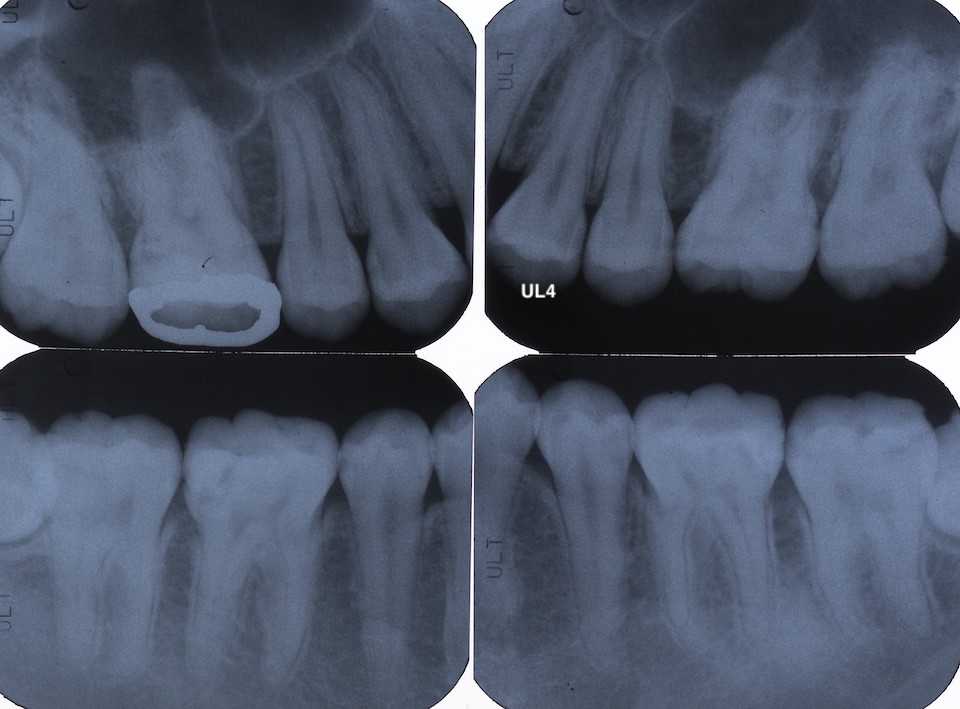

下顎7番の頬側歯茎部カリエスの原因 2025.06.04